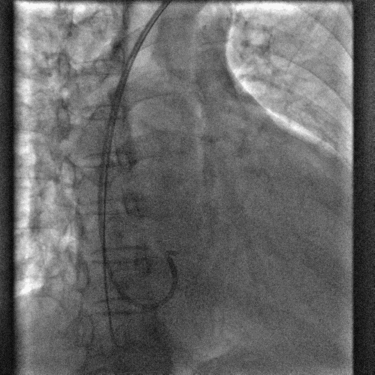

寻找冠状窦

冠状窦口很容易找到,但是外鞘和CS十极很容易弹出

术中冠状窦造影

造影发现在分支静脉处有明显扭曲